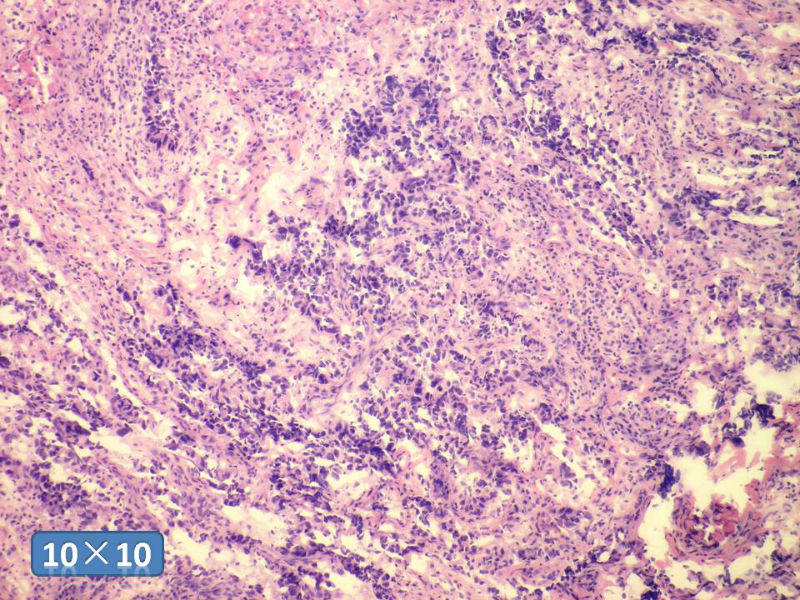

女性,50岁,乳腺肿物,冰冻切片(图1-25)

HE